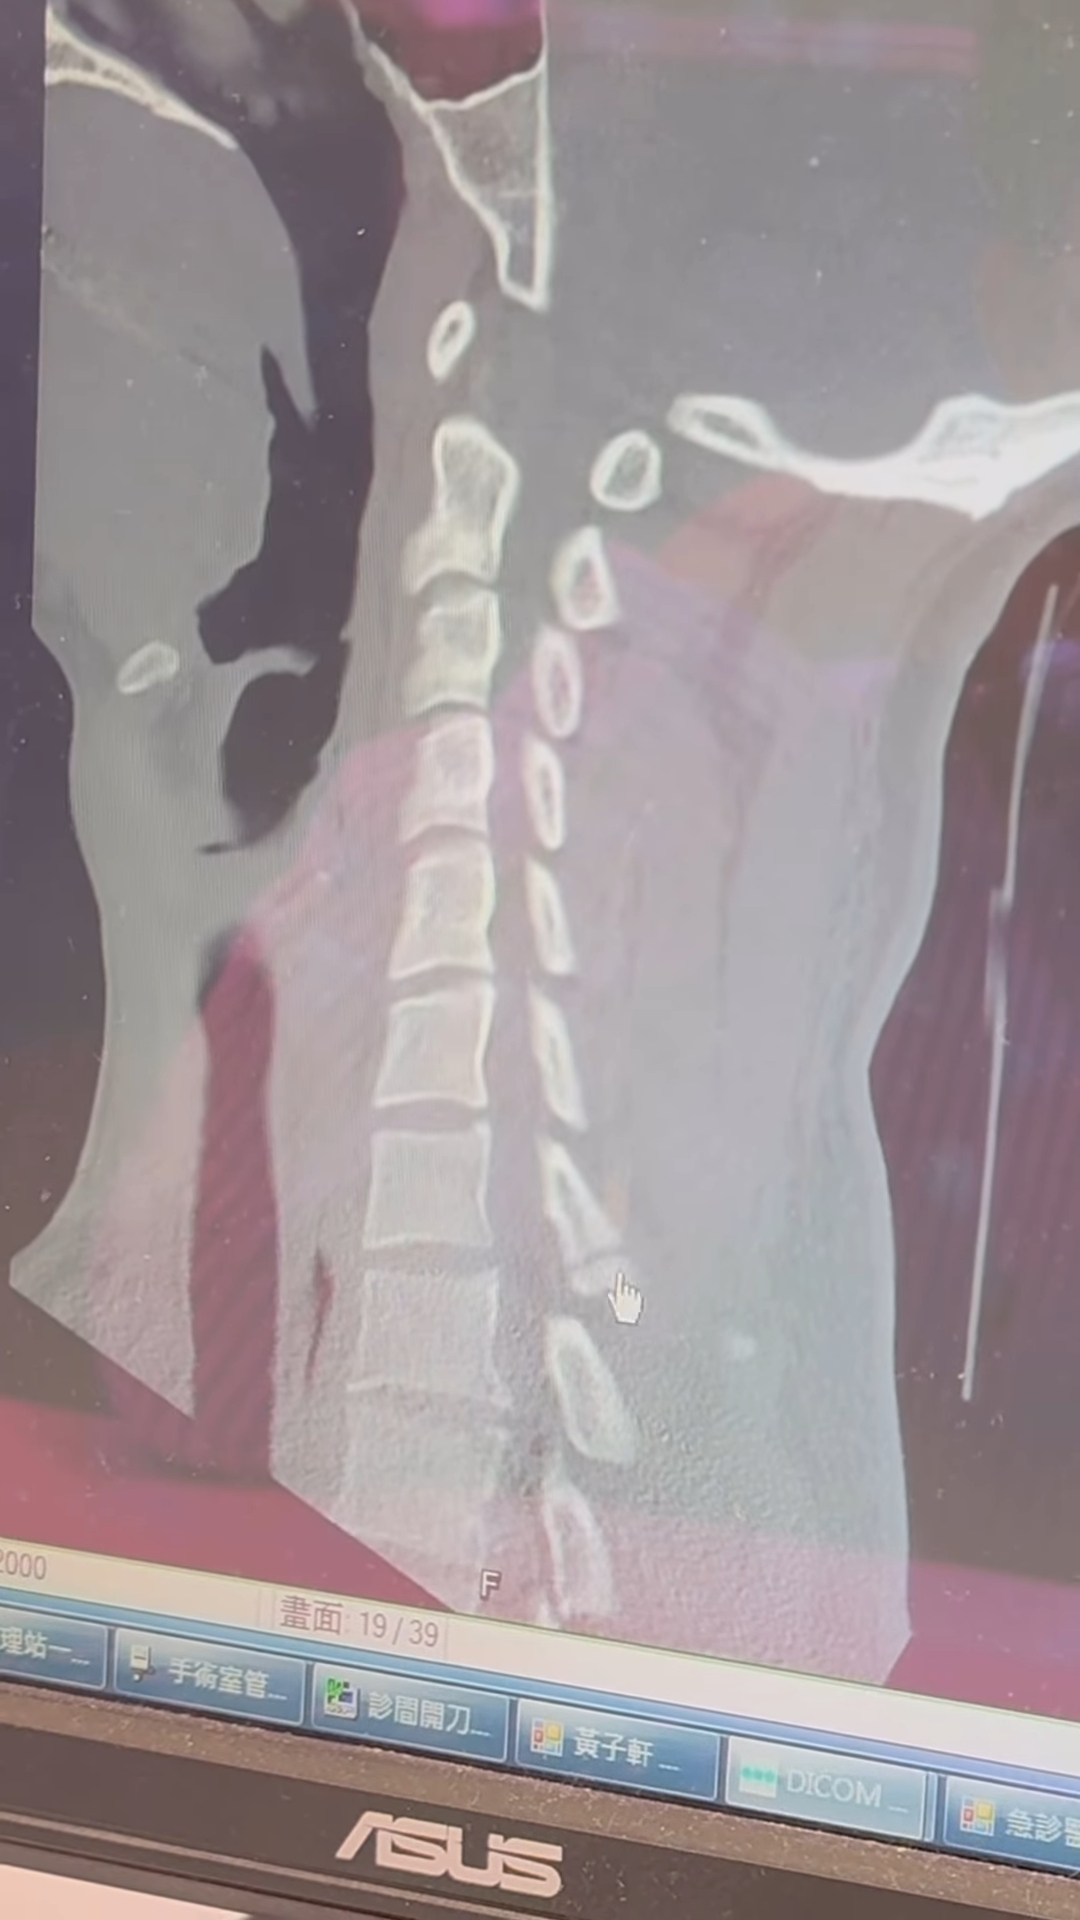

Peeta 12日先是在IG限時動態曬出戴著護頸並躺在病床上的照片,接著發文表示:「我的頸椎裂開了」,只見監視器畫面中,他跟在健身房練習後空翻,怎料疑似是重心沒抓好,頭竟然先落地,一旁的博恩見狀立刻上前關心,隨後就被送往醫院檢查,這才發現意外導致頸椎裂開。

所幸只有造成頸椎裂開,沒有造成更大的意外,Peeta表示:「感謝大家的關心,目前一切正常,只需要休息三個月。之後大家會有段時間會看到我以護頸造型出現。」很感謝老婆、家人跟朋友的陪伴,也謝謝醫護人員的細心照料,他感嘆地說:「還能活動、還能活著真好。我愛大家,我先休息一下。」